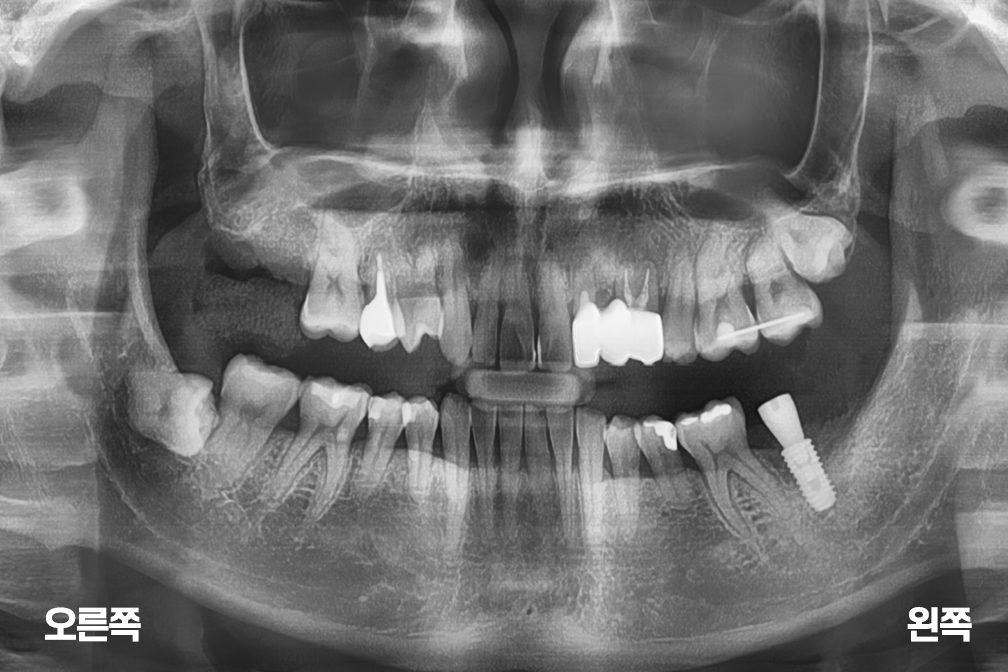

임플란트 오른쪽 윗 어금니 임플란트 및 왼쪽 아래 어금니 보철

After 2021년 9월 16일

위 전후사진은 이미지사진으로 실제 눈으로 보는 것과는 다를 수 있으며, 환자의 치아상태과 방법에 따라 치료결과가 다를수 있습니다.

사진의 날짜는 촬영날짜이며 치료의 기간이 아님을 알려드립니다.

치료 후 치아표면의 탈회 , 충치, 치근흡수 등의 부작용이 있을 수 있습니다.